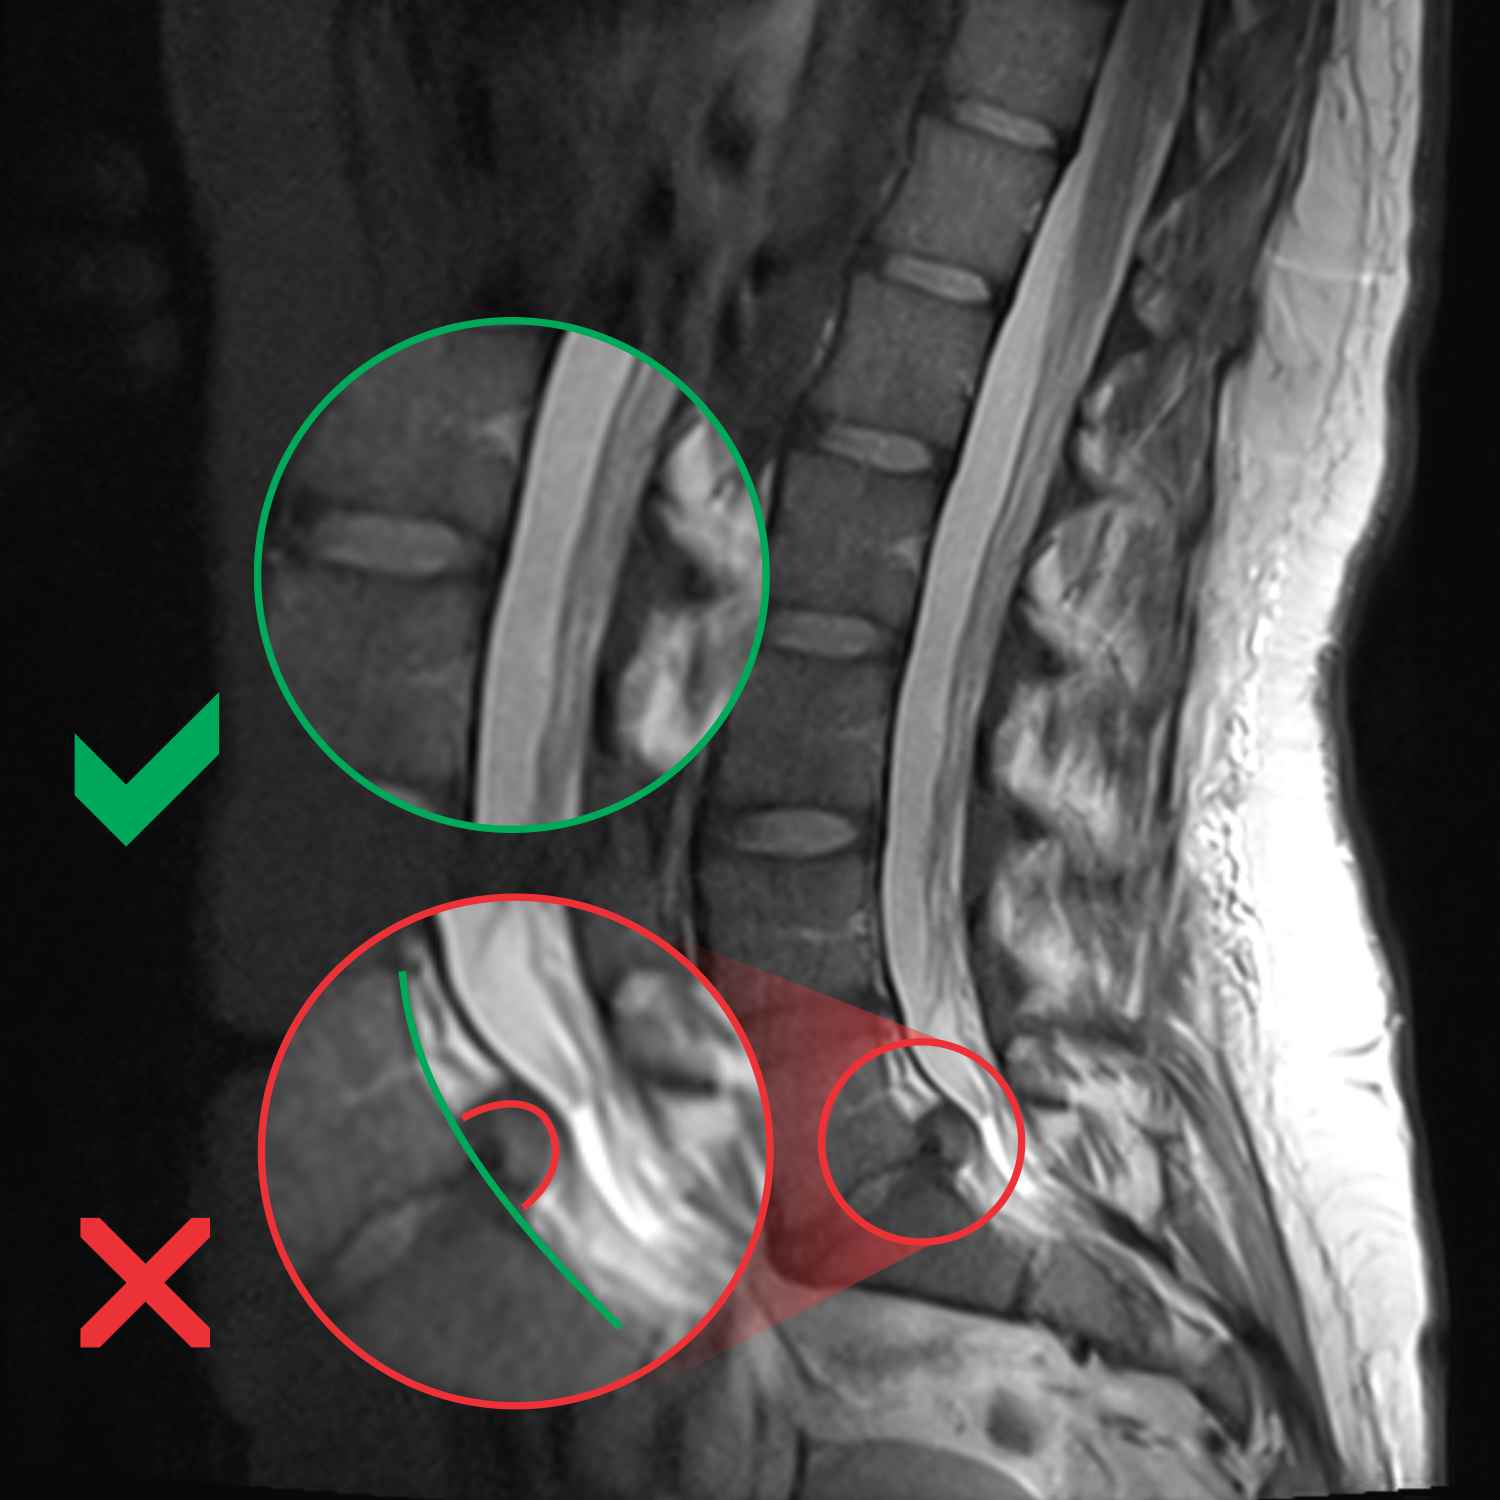

MRI, hernija diska, diskus hernija

Herniacija

Kako prepoznati hernijo diska?

Pri herniji diska so bolečine močnejše, saj se disk izboči in lahko pritisne na živec. Ko močno pritisne, se bolečina seli navzdol po nogi, do stopala, je zelo intenzivna in vas omeji pri kakršnem koli delu, izgubite tudi moč. To so zelo kritične faze. Pri zmerni herniji se bolečina seli v nogo, lahko se tudi malo izboljša, potem pa se ob večjih naporih spet razboli.

Protruzija diska je začetek nastajanja hernije. Kaj je značilno zanjo?

Stvar je popolnoma enaka kot hernija, vendar je manjše intenzitete. Protruzijo in hernijo ločujemo, da vemo, za kakšno stopnjo gre.